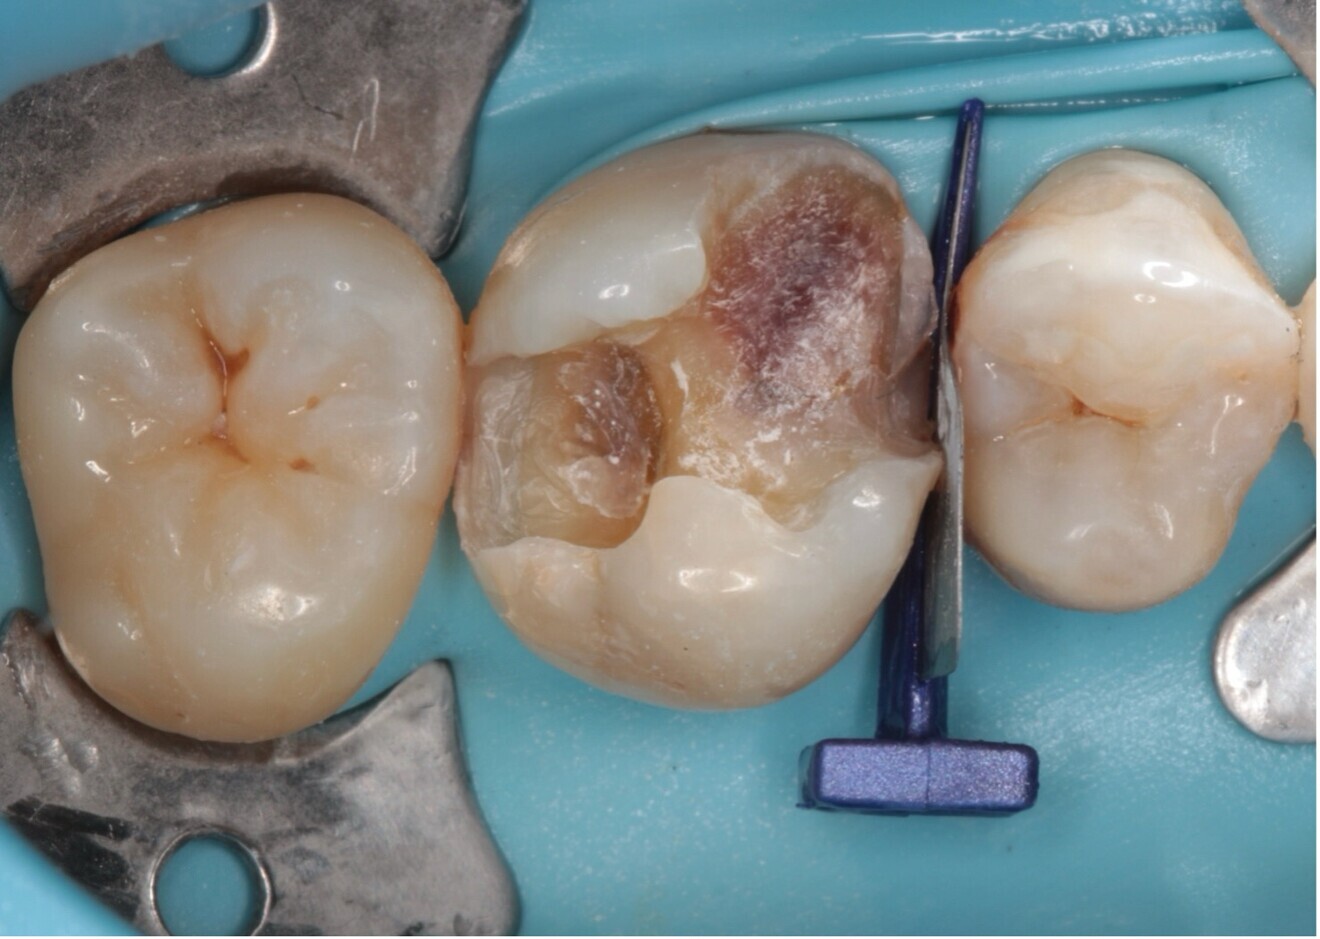

Fig. 5 : La préparation dentaire pour l’assemblage.

Bien que les restaurations adhésives présentent de nombreux avantages, elles ne sont pas toujours adaptées à toutes les situations cliniques. Il est essentiel de distinguer les cas où une préparation adhésive est préférable de ceux où les méthodes traditionnelles de rétention mécanique restent plus appropriées. Les restaurations collées sont idéales pour les patients avec des dents présentant des structures suffisamment solides, pour bénéficier d’une liaison chimique sans compromettre la résistance (Fig. 5). Cependant, dans des cas de perte de structure dentaire importante, ou lorsque la zone de restauration est trop étendue, une couronne complète avec une préparation traditionnelle pourrait être plus indiquée.